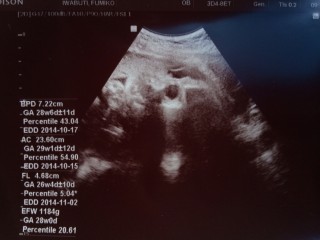

1184gまで大きくなっていました♪